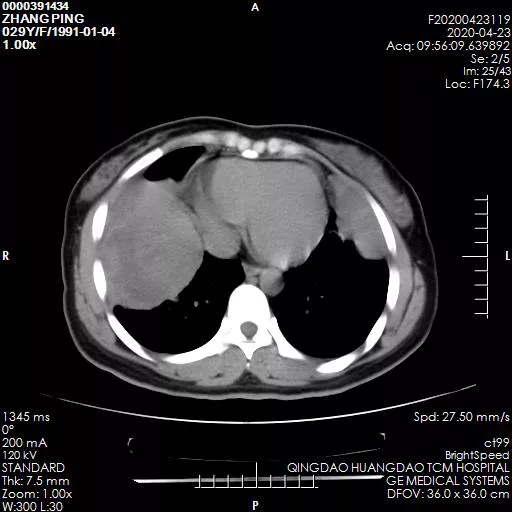

在家人的陪同下,张女士于5月初来到青岛西海岸新区中医医院外二科就诊。谢东副主任医师耐心询问病情,并为其仔细检查,通过CT检查发现右肺有一个铅球大小(10*12cm)的肿瘤,左肺有一6*5cm大小肿瘤。

术前胸部CT示:双肺巨大肿瘤